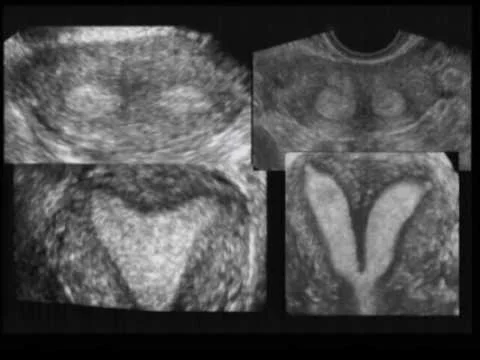

MRI

- Study of normal uterus and ad

- Myoma.

- Adenomyosis.

- Congenital uterovaginal anomalies.

- Gynaecological cancers.

- Pregnancy --- complicated by

- Endometriosis.

- Retroperitoneal lymph node.

Advantages over CT scan and ultrasonography:

- non-invasiveness.

- Without repositioning the patient.

- More sensitivity to flowing